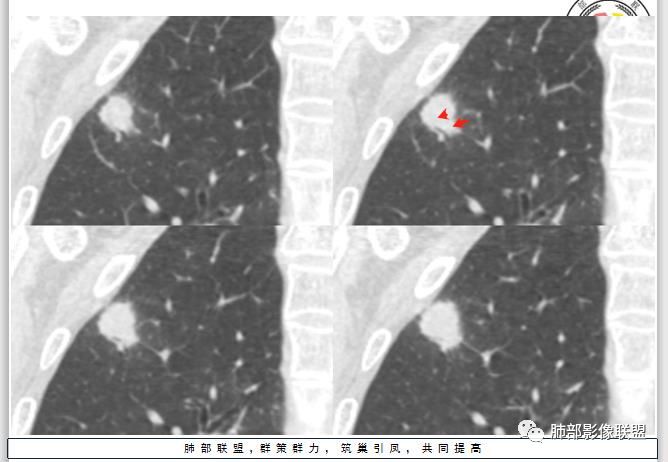

晨读:患者中老年男性,咳嗽 咳痰伴痰中带血2天,发现右上肺结节入院。

胸CT:右上肺结节,病灶位于胸膜下,边缘可见平直 u型征 软毛刺 晕,增强可见延迟强化,病灶中心低密度区。

2.右肺尖类圆形结节影,边界清楚,未见明显分叶或深切迹,部分分边缘较平直,可见细长毛刺棘状突起,相邻胸膜增厚,未见胸膜凹陷。后段胸膜下见条索影及微小结节影。

相关血管未见脐凹,有限图像层面未能显示相关支气管情况。

3.平扫病灶密度密度不甚均匀,外侧份见微小高密度影。

4.增强扫描成明显环形强化,中央液化坏死,内壁清楚且较为规整。